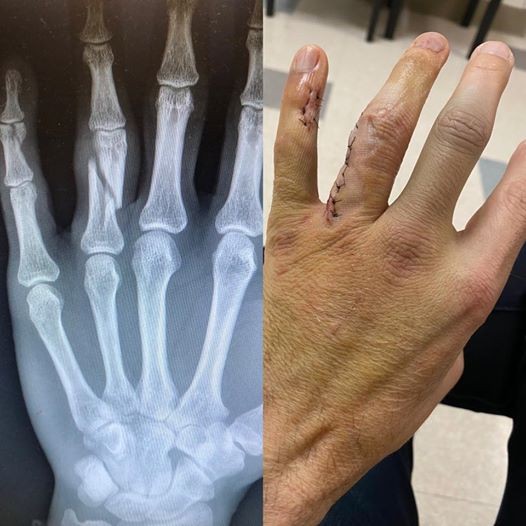

Le guitariste de Papa Roach, Jerry Horton, a partagé avec ses fans aujourd'hui (12 février) qu'il s'est cassé deux doigts à la main gauche. En raison de l'accident, le guitariste / claviériste Anthony Esperance prendra la place de Horton pour les dates européennes de 2020 du groupe.

Horton n'a pas expliqué comment il s'était cassé la main, mais le musicien a montré une radio de sa main gauche, montrant que son annulaire est essentiellement cassé en deux. Une autre photo montre qu'Horton a reçu un certain nombre de points de suture à l'annulaire et au petit doigt.